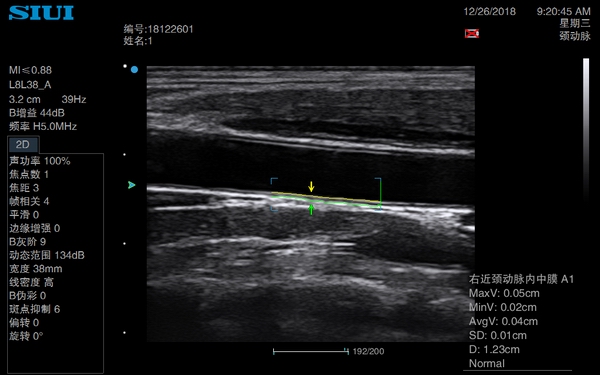

Auto IMT ( Intima-Media Thickness) Measurement:

The system can automatically measure the Intima-Media Thickness of the carotid artery wall, so as to evaluate cardiovascular diseases such as hypertension diabetes.